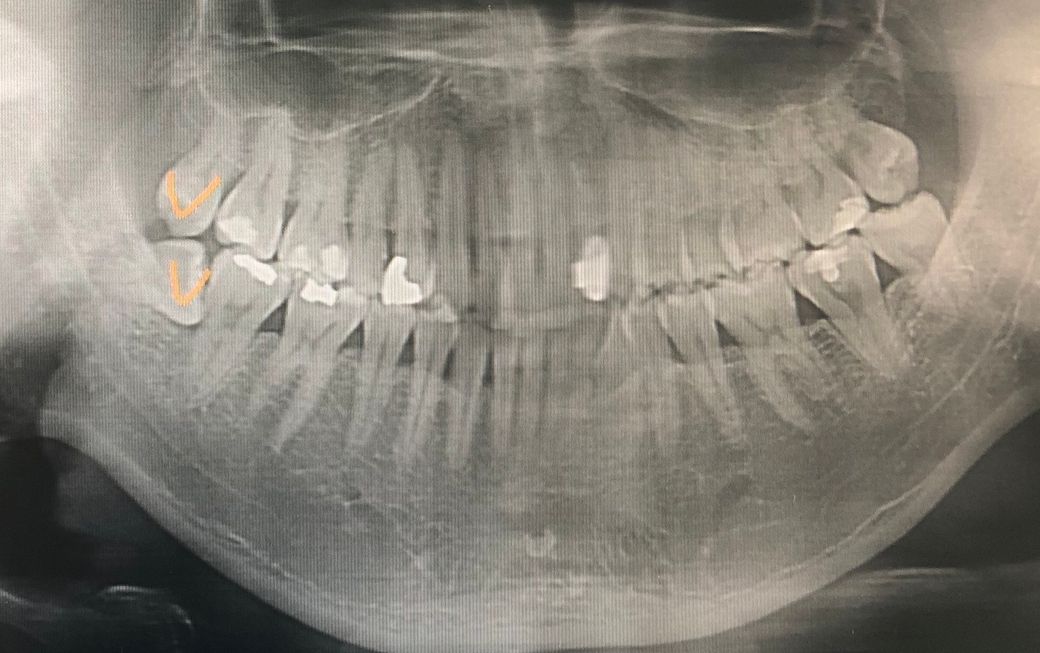

치과 엑스레이 사진 잇몸 상태 어떤가요?

사랑니 뺄려고 찍은 사진인데 뭔가 잇몸쪽에 선이 직선으로 있어야 할거같은데 울퉁불퉁 한거같아서 걱정인데요..안좋은 상태인가요?

사진으로 봤을 경우에는 잇몸에 큰 문제는 없어보입니다.

원래 치아를 잡고 있는 잇몸뼈는 울퉁불퉁하게 보일수 있어요.

잇몸뼈상태는 엑스레이상으로 크게 문제가 있어 보이진 않습니다. 지금처럼 관리를 잘하시면될것같습니다.

질문하신 분의 나이가 나와있지 않지만 양쪽 아래 어금니의 잇몸뼈가 조금 내려간 상태입니다. 더 이상 내려가지 않게 하거나 내려가는 속도만 늦출 수 있습니다. 주기적으로 스켈링 받고 평소에 꼼꼼한 치솔질 하시기를 추천합니다.

치아 사이 잇몸뼈는 x-ray 상에서 울퉁불퉁 하게 보이는 것이 정상이며, 잇몸 뼈의 상태에는 문제가 없어 보이므로 걱정 안하셔도 괜찮습니다